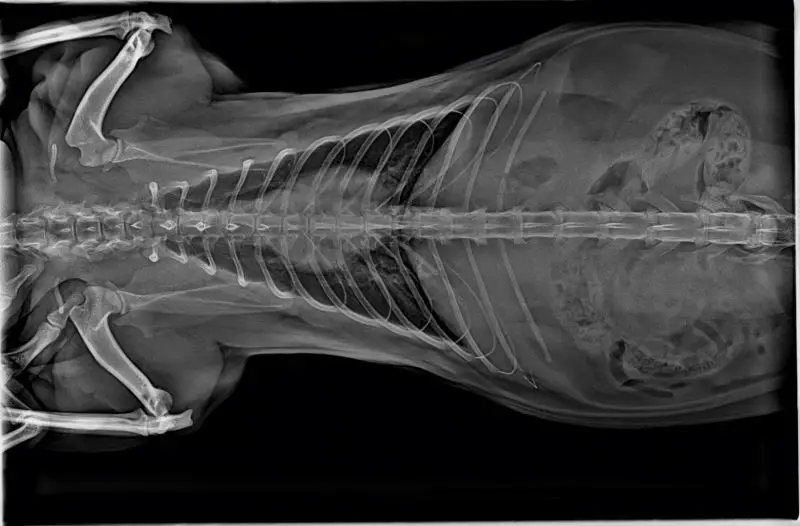

Veterinary DR System Digital Flat Panel X Ray Detector Pet Clinic Dynamic X Ray Equipment Medical Instrument Vets